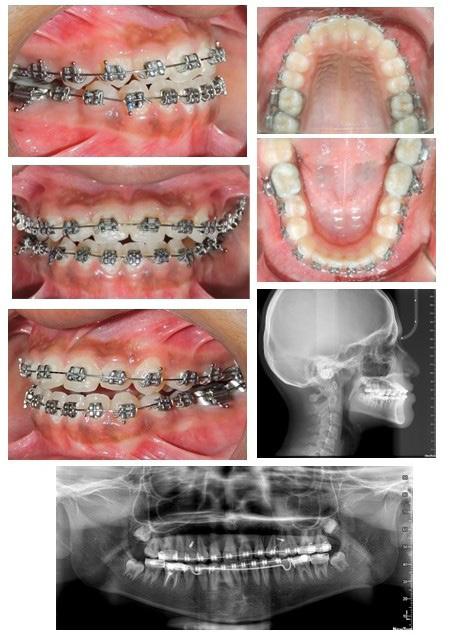

Standard orthodontic pretreatment records (T0) were obtained (Figure 1). The same operator obtained the lateral cephalogram and OPG using the same machine. The lateral cephalograms were traced manually with the standard technique by a single

investigator and a total of 06 skeletal, 11 dental, and 03 soft tissue parameters were measured. Selected patients were also subjected to Acoustic pharyngometry (AP) for a three-dimensional evaluation of the upper airway. Fixed orthodontic appliance (022” MBT PEA) was bonded on both maxillary and mandibular arch, with banding of first & second molars. A standard wire sequence was followed till the full slot engagement with SS wire (19 X 25”) was achieved. A complete set of records were made to register the beginning of the fixed functional phase (T1) (Figure 2). Forsus appliance (FFRD) was fitted for each patient, push rod hooked on the archwire between canine and 1st premolar in the maxillary arch and distal end of open coil spring connected with the ‘L’ pin to the 1st mandibular molar. Maxillary and mandibular components of the Forsus FRD were connected to provide a forward thrush to the maxilla and a backward thrust to the mandible during the closure of the mouth (Figure 3). The functional phase with Forsus FRD continued till the desired objectives were achieved i.e., achieving positive overjet as well as satisfactory improvement in soft tissue profile.

To enhance the skeletal effects of the Forsus appliance, the indirect anchorage was obtained using TADs (temporary anchorage devices), placed in the maxillary arch, distal to canine. Post-functional records were made after the removal of Forsus FRD (T2) (Figure 4). Fixed orthodontic therapy continued to settle the occlusion and patients were debonded (Figure 5).

Figure 1:Pre-treatment Orthodontic records

Figure 2: Pre-functional Orthodontic records

Figure 4: Post functional orthodontic records

Figure 5: Post-treatment Orthodontic records

Figure 3: Forsus appliance in situ